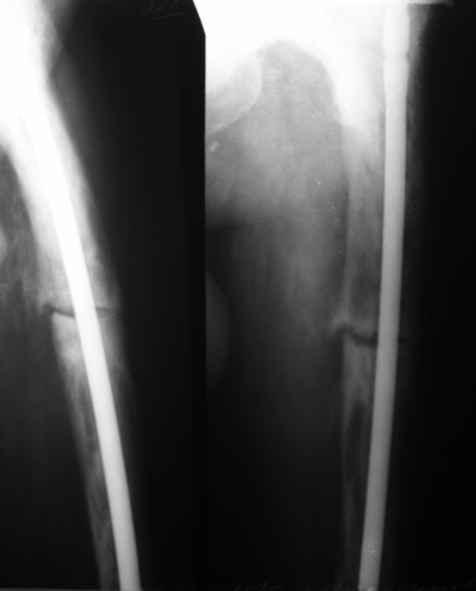

Анатолий Леонидович Баранецкий совершенно прав. Сращения ждать надо очень долго (несколько лет). Главное - гвоздь попрочнее и потолще. Раньше использовали мощный 4-гранный штифт ЦИТО. Можно и гвоздь с блокированием (блокировать только с одной стороны) - но ни в коем случае не полый. И ходить с тростью. Сейчас в России зарегистрирован очень хороший препарат (с декабря 2006 г.) - Акласта, по 100 мл - обычно хватает 1 (реже двух) инфузии для полной ремиссии (в Белоруссии он появился даже раньше, чем на Украине и в Россиии). Немного хуже Аредия, ее надо в сумме 180-240 мг, полная эффективность 84%. Все в\в кап. бисфосфонаты вызывают выраженную гипокальциемию. Поэтому приходится назначать по нескольку лет альфакальцидол под контролем Са крови (каждые 3-6 мес). Сперва по 6-8 капсул (капель), т.е 1,5-2,0 мкг, затем через 2-4 месяца - по 0,5-0,75 мкг. Препараты Са по 1-2 гр. в день, очень долго.

Кстати, при метастатических поражениях костей или вторичном остеопорозе на фоне лейкоза можно перелить Зомету (это тот же золедронат, что и Акласта, только зарегистрированный по-другому).